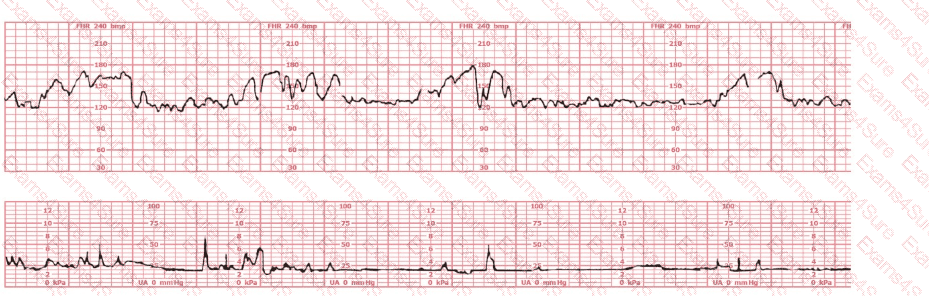

This external tracing is from a 19-year-old (G1P0) at 39-weeks gestation. She is 6 cm dilated, 100% effaced, and –2 station. The fetus is in an occiput posterior position. She rates her pain as 8. She reports being lightheaded. She is most likely at risk for respiratory: